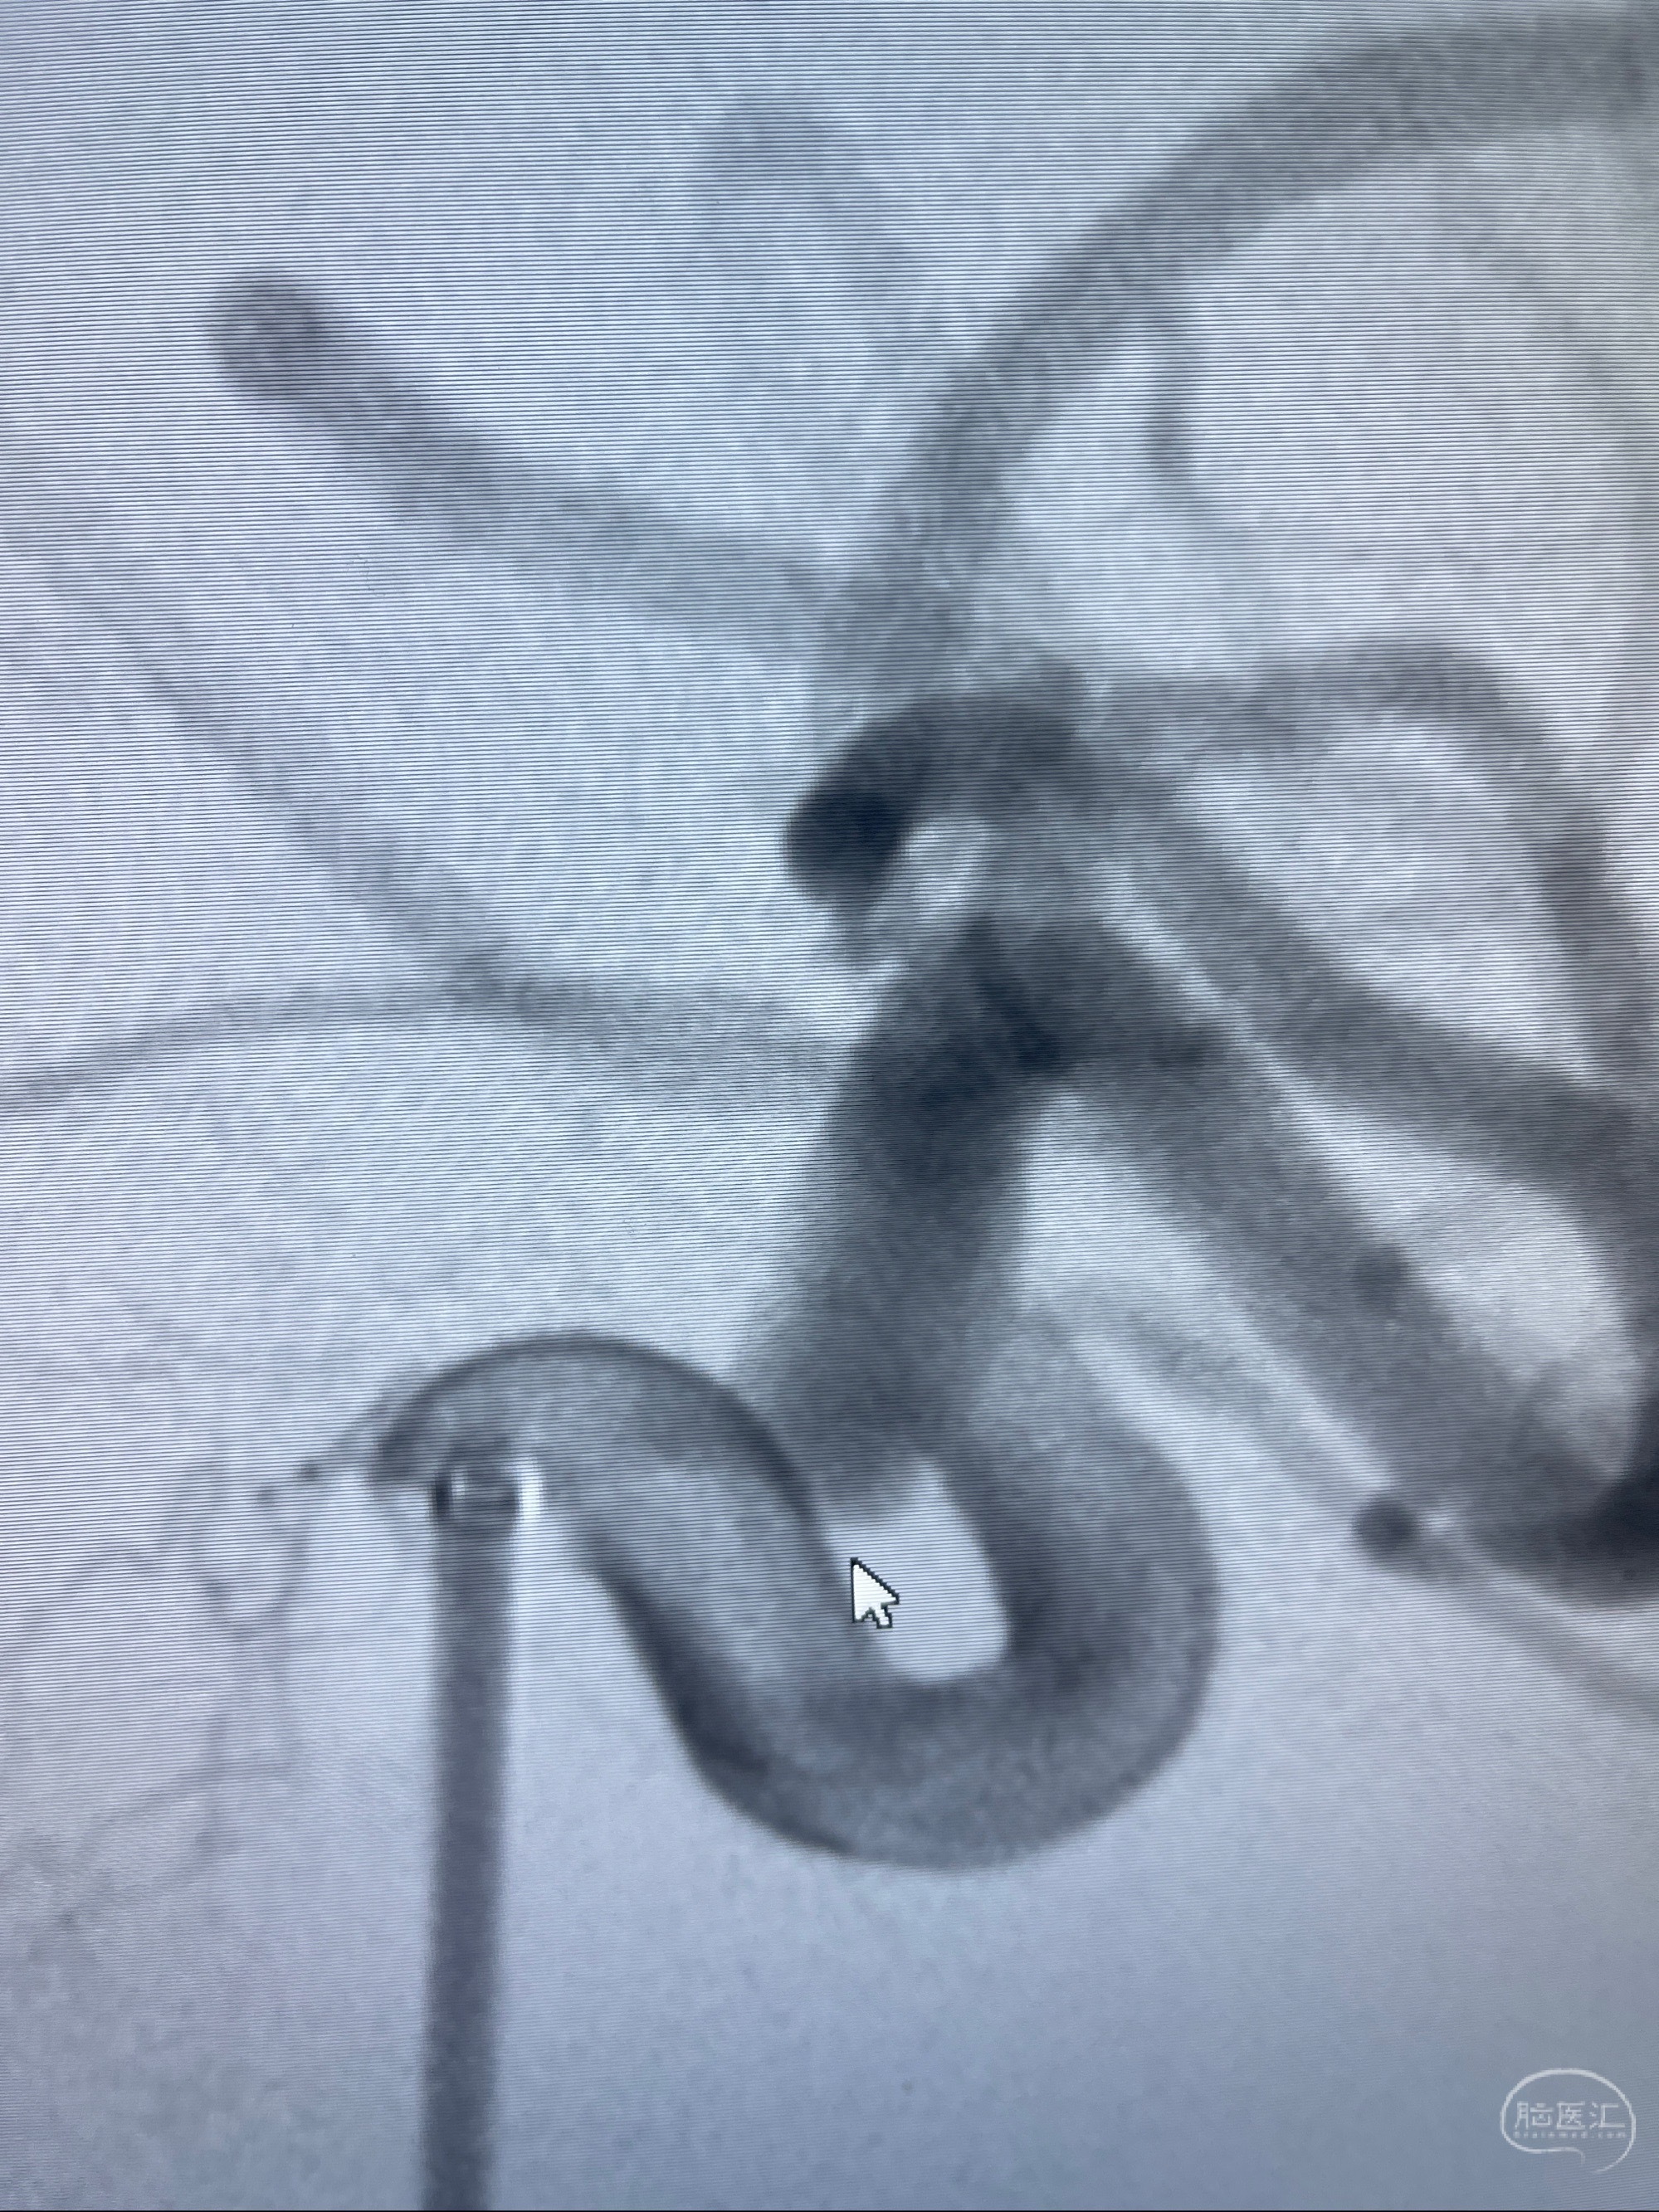

2023-08-01全麻下行双侧颈眼动脉瘤支架辅助栓塞

- pipeling4.5-20mm

- pipeline 4.0-20mm

手术顺利,麻醉苏醒佳,遵嘱动作